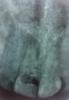

samedi Опубликовано 25 марта, 2011 Автор Поделиться Опубликовано 25 марта, 2011 (изменено) а не ходить по виртуальным страницам форумов различных мед специальностей.но у вас тут так хорошо))) сходил сегодня, сказали что серьёзно всё и кариес в каналах... типо или как-то там) сделали снимок, так промыли какими-то антисептиками каналы.. сказали что канал хороший и маленький.. было немного больно сперва и я настоял на обезбаливающем.. по плану лечения, сегодня поставили метапасту, и временную пломбу.. или как-то так.. потом через 10 дней придти ещё раз и повторить процедуру, если пойдёт на улучшение то всё супер. Сказали что возможно напухание десны повторно, и нужно будет снова вскрывать десну для ослабления нагрузки на ткани... вот собственно снимок, которого так не хватало.. но я там ничего не понял и вообще не понял что за снимок)) там чёрное пятнышко посредине зуба или чего-то зубоподобного - это я нечаянно неудачно доставал из упаковочки снимок.. а он там был толи приклеен, толи что... зуб 11, верхний, передний. что скажете, уважаемые? Изменено 25 марта, 2011 пользователем samedi Ссылка на комментарий

DokDent Опубликовано 25 марта, 2011 Поделиться Опубликовано 25 марта, 2011 но у вас тут так хорошо))) сходил сегодня, сказали что серьёзно всё и кариес в каналах... типо или как-то там) сделали снимок, так промыли какими-то антисептиками каналы.. сказали что канал хороший и маленький.. было немного больно сперва и я настоял на обезбаливающем.. по плану лечения, сегодня поставили метапасту, и временную пломбу.. или как-то так.. потом через 10 дней придти ещё раз и повторить процедуру, если пойдёт на улучшение то всё супер. Сказали что возможно напухание десны повторно, и нужно будет снова вскрывать десну для ослабления нагрузки на ткани... вот собственно снимок, которого так не хватало.. но я там ничего не понял и вообще не понял что за снимок)) там чёрное пятнышко посредине зуба или чего-то зубоподобного - это я нечаянно неудачно доставал из упаковочки снимок.. а он там был толи приклеен, толи что... зуб 11, верхний, передний. что скажете, уважаемые?Изменение на корне есть,обострение может дать.Метапаста-это нормально.Скиньте потом снимок после пломбировки. Ссылка на комментарий

samedi Опубликовано 25 марта, 2011 Автор Поделиться Опубликовано 25 марта, 2011 (изменено) это снимок до или после лечения? с метапастой достаточно 2 недель и не требуется повторная закладка препарата. потом сразу пломбируют канал.это до лечения, перед пломбировкой временной, сказали через 10 дней повторить.. и если будет всё хорошо, то окончательно запломбируют, и потом наблюдаться раз в месяц на предмет воспаления.зменение на корне есть,обострение может дать.да.. сказали что есть, и может быть обострение, если будут проблемы, то будут делать резекцию корня верхушки.. после пломбировки окончательной? для просмотра (успешности/и не оченть) результата?спасибо за ответы) вы очень приветливые и грамотные специалисты.. спасибо) Изменено 25 марта, 2011 пользователем samedi Ссылка на комментарий

DokDent Опубликовано 25 марта, 2011 Поделиться Опубликовано 25 марта, 2011 это до лечения, перед пломбировкой временной, сказали через 10 дней повторить.. и если будет всё хорошо, то окончательно запломбируют, и потом наблюдаться раз в месяц на предмет воспаления. да.. сказали что есть, и может быть обострение, если будут проблемы, то будут делать резекцию корня верхушки.. после пломбировки окончательной? для просмотра (успешности/и не оченть) результата?спасибо за ответы) вы очень приветливые и грамотные специалисты.. спасибо) Ну для оценки результата такой срок маловат ,а для того,чтоб оценить качество заполнения канала (что является ключевым моментом для достижения положительного результата). пломба какая-то не очень.. уже к вечеру маленький кусочек отвалился.. а она не вывалится за пару дней?Попросите доктора поставить пломбу покрепче.Это важно. Ссылка на комментарий